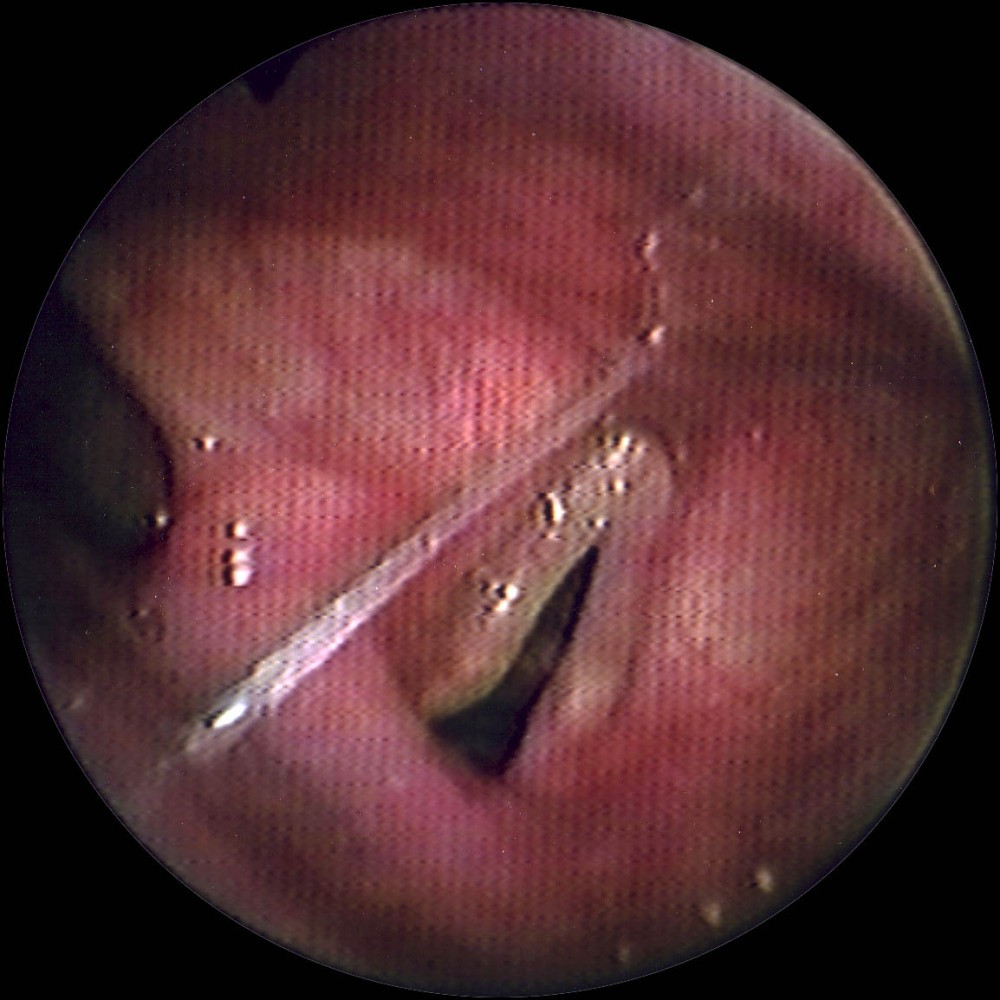

注:以上相片為示意圖。